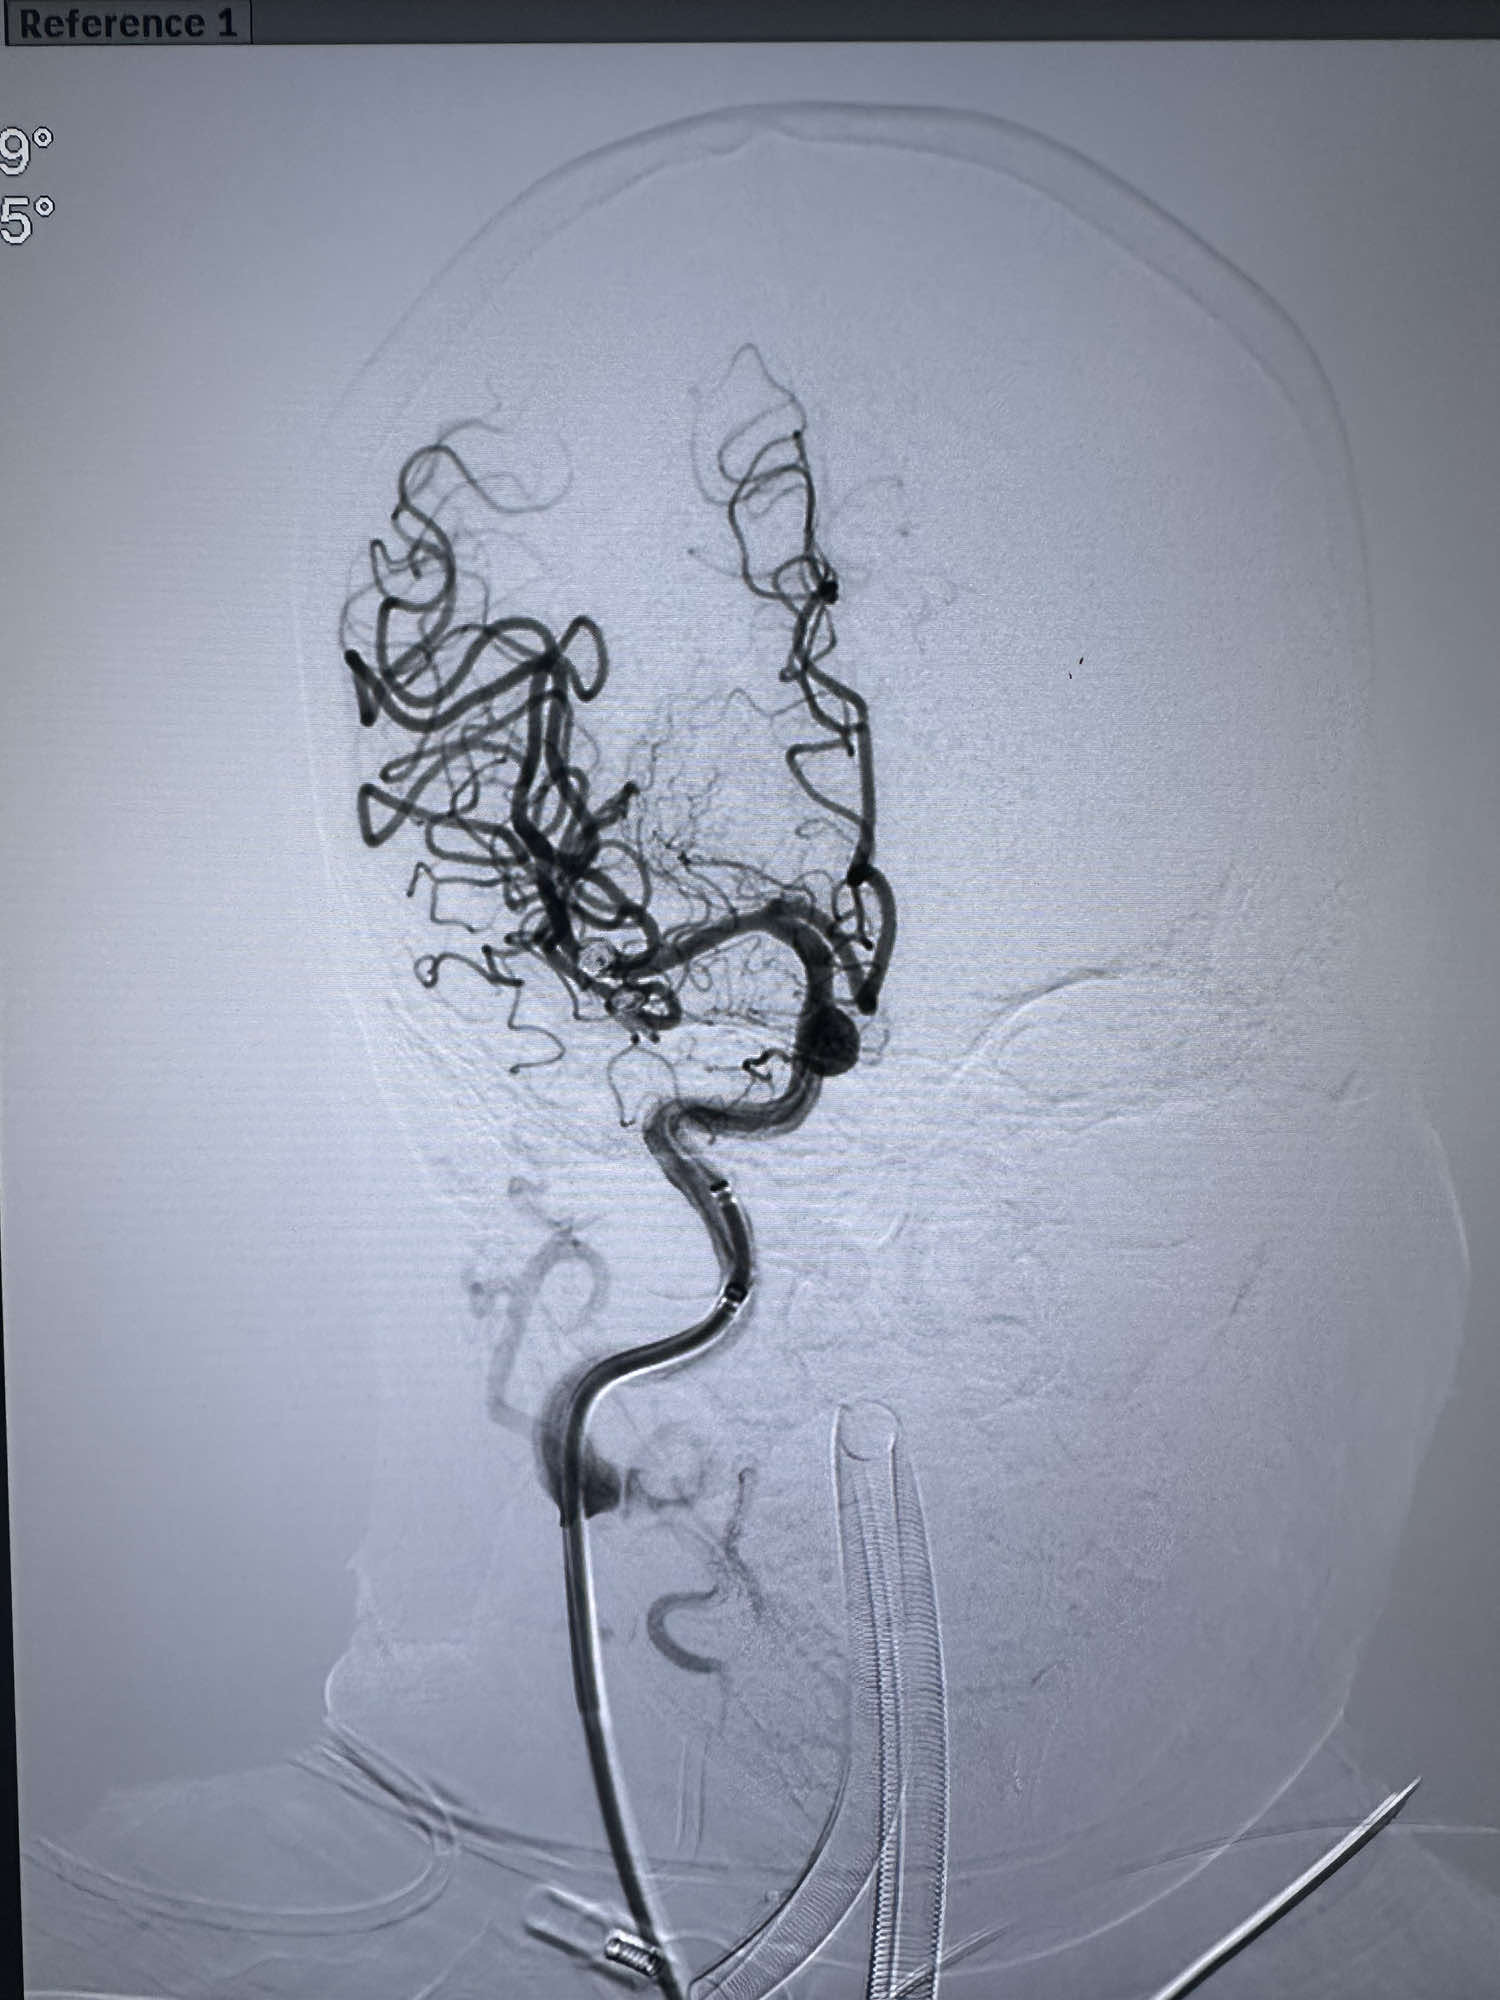

最后造影显示动脉瘤不显影

最后正位造影